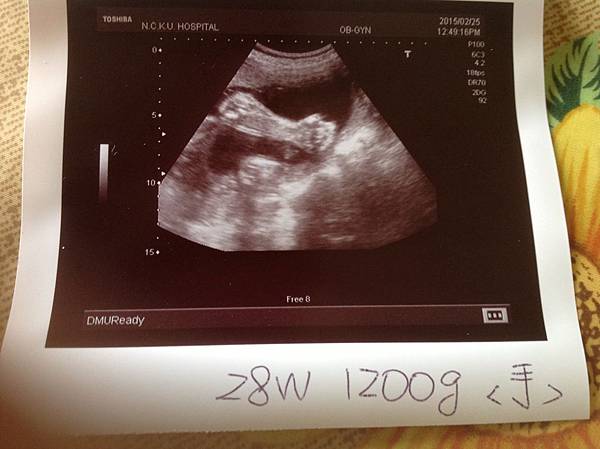

羊咩28W 年後產檢

過完年才產檢,這對孕婦來說壓力很大,因過年期間少不了大吃大喝,目前孕期體重總增加了10kg!

還好這次醫生護士衛教師,都不敢對這時期產檢的媽咪有任何指責,沒辦法過年一定無法克制飲食的呀!

好久沒看見羊咩的臉了,今天特別提醒醫生,照得到臉嗎??

醫生想也知道,是媽咪想幫羊咩留記念,所以想拍臉,可惜,羊咩把臉埋起來,不給拍就是不給拍。